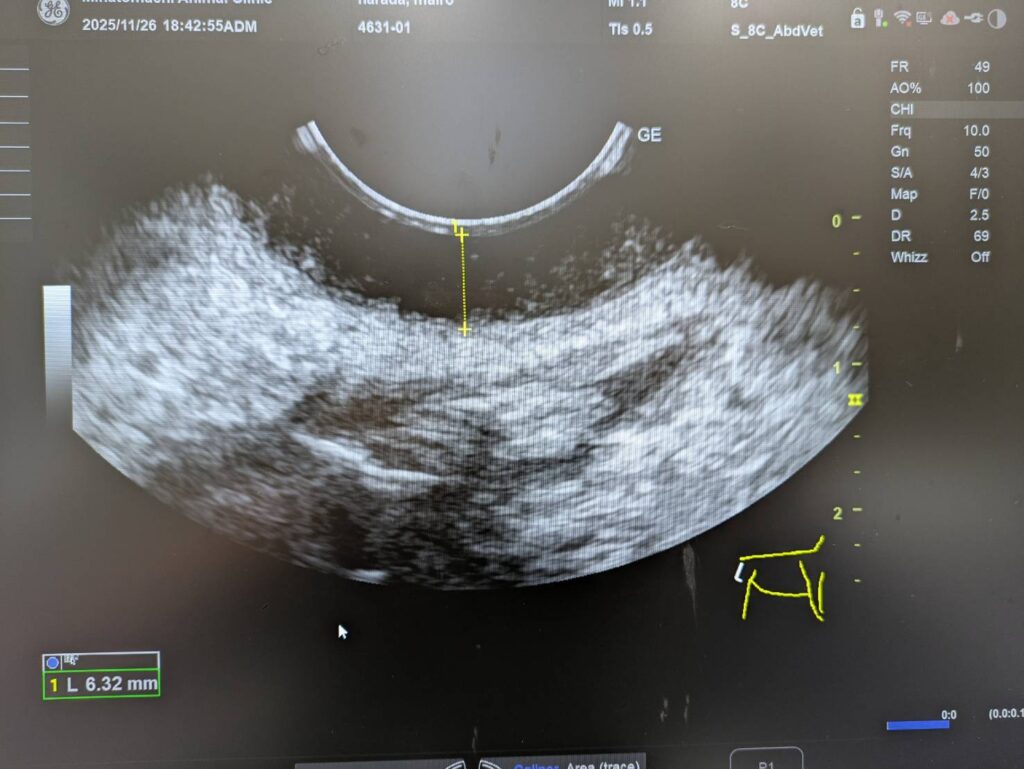

エコーで腫脹した部分を検査させてもらうと

こんな感じで、腫大を認める部分が黒く抜けており

普通の皮膚疾患ではなさそうだったので

後日細胞診を実施することに。

皮膚のエコー検査に関しては

大阪の福間先生に教えてもらった検査なのですが